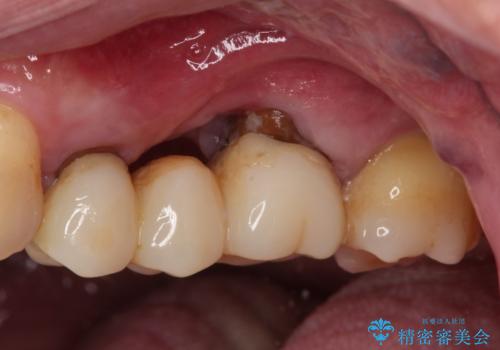

ものが挟まって痛む 割れてしまった歯のオールセラミックブリッジ治療

- 奥歯に物が挟まり、痛みを感じるとのことで来院された患者様です。

レントゲン写真より、歯が破折している可能性が示唆され、歯槽骨が大きく欠損している様子が分かりました。

3歯のクラウンを除去し、破折が疑われる歯をチェックしたところ、予想通り破折していたため、抜去することとしました。

抜歯後、骨吸収量が多く、歯肉のラインが不揃いとなっているため骨造成術を、硬い歯肉が失われて清掃性が低下するため角化歯肉の移植術を行い、また並行して支台歯の根管治療を行っていき、環境を整えた上でオールセラミックブリッジにて補綴治療を行うこととしました。